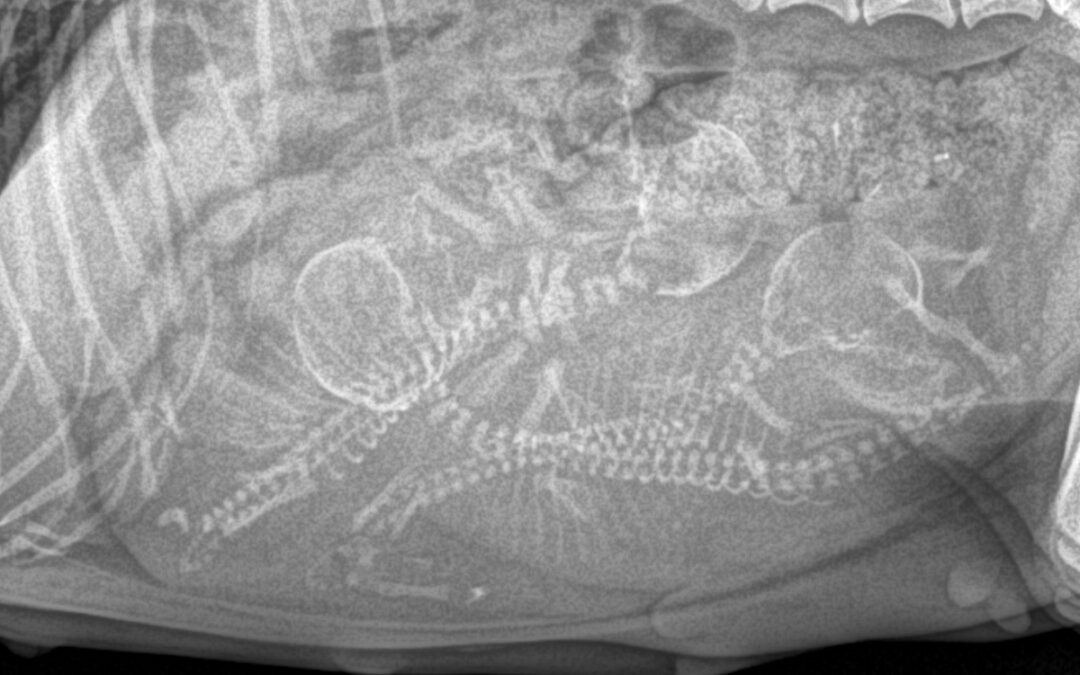

Book Online (03) 9115 4647 Back to Vet Services Medical Imaging Veterinary Medical Imaging, Digital X-Rays & Ultrasound For Pets X-ray image of Peanut the Chihuahua’s pregnancy Medical imaging helps us to look at what’s going on inside your pet without...